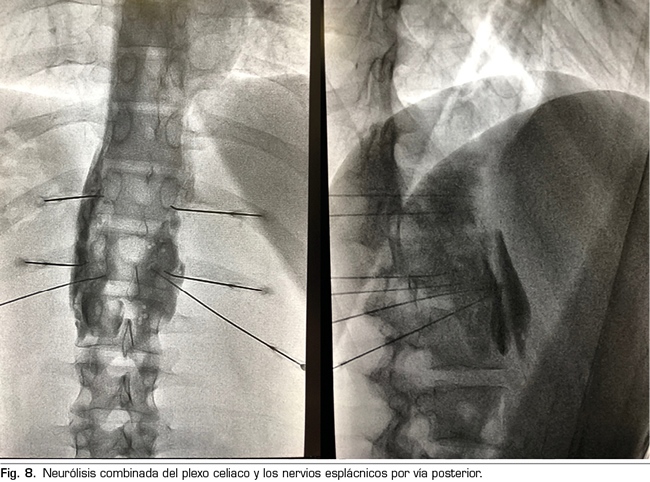

El procedimiento estándar sería el abordaje posterior del plexo celiaco (abordaje clásico), ya que a día de hoy continúa siendo el de mayor evidencia científica, preferiblemente transcrural y guiado por fluoroscopia, debido a su sencillez y rapidez. La ecoendoscopia estaría indicada para la neurólisis aprovechando su indicación diagnóstica o terapéutica, para situaciones de imposibilidad para el decúbito prono, y como alternativa en caso de que falle el abordaje posterior. La neurólisis percutánea ecográfica quedaría reservada para casos seleccionados, dependiendo de la experiencia del operador, ya que es la técnica que menos publicaciones tiene hasta la fecha. Confiamos en que en un futuro se publiquen trabajos que permitan a las técnicas ecoguiadas, ya sean percutáneas o ecoendoscópicas, ocupar el puesto de “método de referencia”, ya que permiten la visualización de las estructuras circundantes con control de la inyección en tiempo real. Una alternativa al bloqueo del plexo celiaco es la radiofrecuencia convencional de los nervios esplácnicos, indicada cuando existe infiltración tumoral del tronco celiaco, alteraciones anatómicas importantes o si fracasa la neurólisis del plexo celiaco. También es posible considerar una neurólisis combinada —bloqueo neurolítico del plexo celiaco asociado a bloqueo neurolítico o radiofrecuencia de los nervios esplácnicos—, como refleja el trabajo de Marra y cols. (60), y como venimos realizando en nuestra práctica clínica habitual en HM hospitales, con el objetivo de aumentar la tasa de éxito y la duración de la analgesia sin aumentar la incidencia de complicaciones, pero hasta ahora no hay trabajos comparativos suficientes para apoyar esta hipótesis (Figura 8).